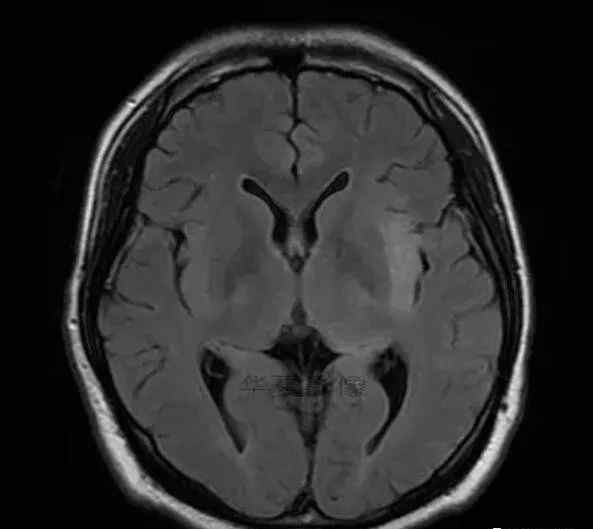

1.左侧颞叶、海马和岛叶T1WI信号低,T2WI信号高

2.病变没有明显的边界

3.占用效果不明显

4.豆状核不受影响